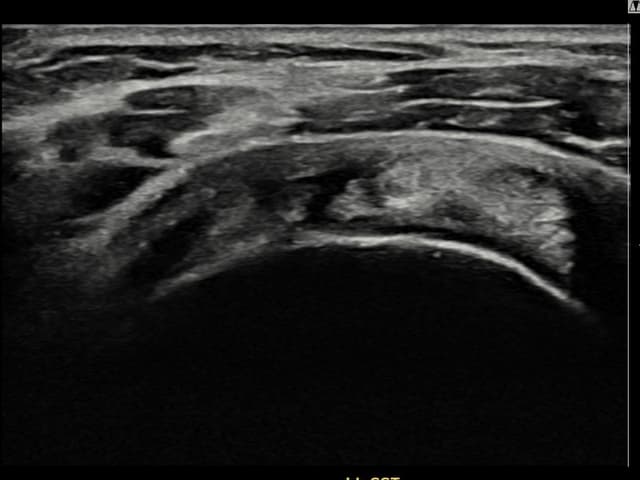

右侧 冈上肌腱 石灰化肌腱炎

10mm × 7mm